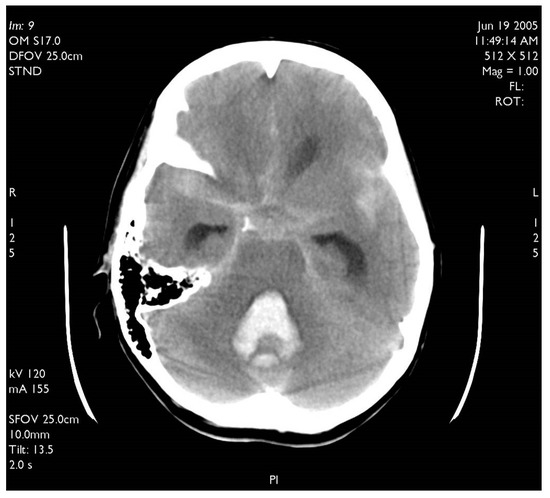

Figure 4. Typical CT scan of subarachnoid hemorrhage (SAH) in posterior fossa with hemocephalus in the fourth ventricle.

A 60-year-old woman was admitted for abrupt loss of consciousness. CT in a peripheral setting showed cerebellar hemorrhage with a pan-intraventricular hematoma in the fourth ventricle and a massive SAH in the cerebellar and spinal canal regions (Figure 4). AG revealed three aneurysms on the distal PICA (Figure 5), successfully excluded from circulation by microsurgery clipping while maintaining patency of the PICA. During the surgery, sudden intraoperative rupture occurred from the most peripheral aneurysm, located just under the arachnoid membrane on the surface of the cerebellum. After easy clipping of the neck, the feeding vessel was followed in the hematoma to its telovelotonsillar part, where another two aneurysms were visible. With the technique of temporary clipping, the optimal final position on both clips was achieved in the wide necked aneurysms. The patency was confirmed with intraoperative ultrasound. A difficult postoperative course and hydrocephalus required temporary ventricular drainage, which was converted to a ventriculo peritoneal (VP) shunt with a good long-term result.